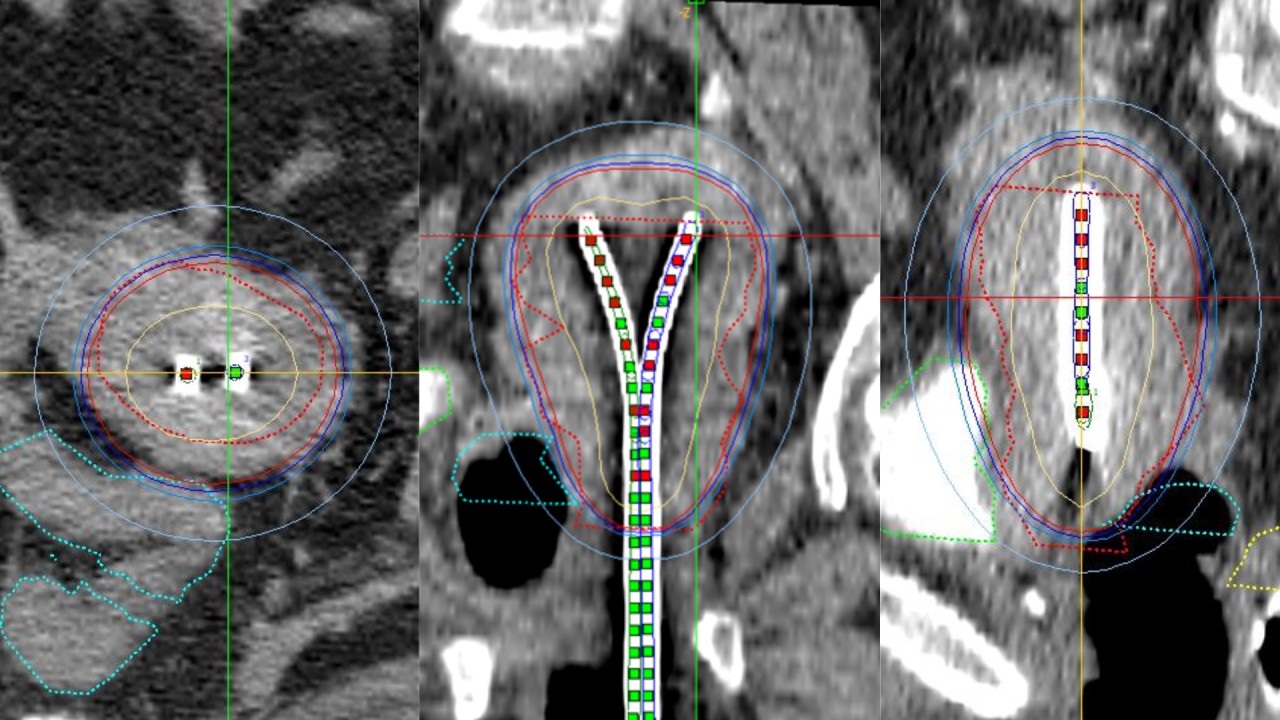

Երբ վիրահատությունը հնարավոր չէ․ բրախիթերապիան որպես արդյունավետ լուծում

83-ամյա պացիենտը դիմել էր Ուռուցքաբանության ազգային կենտրոն սեռական ուղիներից առատ արյունահոսության, ցավերի և ընդհանուր թուլության գանգատներով։Համալիր հետազոտություններով ախտորոշվել էր արգանդի մարմնի